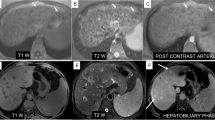

Large regenerative nodules are benign multiacinar regenerative nodules, usually multiple, containing more than one portal tract, located in a liver which is otherwise abnormal, either with cirrhosis or with severe portal vein disease, hepatic veins or sinusoids. Large regenerative nodules are distinctly larger than the majority of cirrhotic nodules in the same liver, at least 5 mm in diameter (International Working Party 1995). They are also associated with some systemic disease, such as chronic vascular disease (polyarteritis nodosa), rheumatologic disease (Felty syndrome, rheumatoid arthritis, scleroderma, telangiectasia), systemic lupus erythematosus, lymphoproliferative disorder (Hodgkin lymphoma and non-Hodgkin lymphoma, chronic lymphocytic leukemia), myeloproliferative disorder (polycythemia vera, chronic myeloid leukemia, myeloid metaplasia), hepatic vascular disease (Budd Chiari syndrome, sinusoidal obstruction syndrome) and drugs (steroids, chemotherapy, immunosuppressors and contraceptives) (Wanless 1990; Stromeyer and Ishak 1981). In contrast to NRH, LRNs are clearly depicted at imaging since, on MRI, they appear hyperintense to the liver in T1-weighted images due to the presence of copper within the nodules, and isointense or hypointense on T2-weighted images (Wanless et al. 1990). On post-contrast CT and MRI, LRNs typically enhance in the arterial phase and might potentially be misdiagnosed as HCCs; the differential diagnosis relies on the persistent enhancement in the portal and delayed phases with absent washout in LRN unlike HCC (Vilgrain et al. 1999; Takayasu et al. 1994). However, there is little evidence to suggest that LRNs are premalignant or evolve into HCC (Stromeyer and Ishak 1981). In the HB phase of MRI, hyperplastic hepatocytes, such as those in LRNs which often contain ductular proliferation (Tanaka and Wanless 1998), appear isointense or more often hyperintense as compared to the normal parenchyma, unlike HCC (Fig. 4) (Renzulli et al. 2011).

Large regenerative nodule on MRI. T2-weighted image (a) demonstrating no hyperintense focal lesions. T1-weighted “in-phase” (b) and “out-of-phase” (c) images revealing a hyperintense nodule at segment VII (arrows). Arterial phase (d) showing nodule hyperenhancement, persistent (arrows) during the portal phase (e), additionally increasing in the hepatobiliary phase (arrow) (f)

6 Hemangioma in Cirrhosis

Liver hemangiomas are the most common primary benign liver lesions; they are usually small and are encountered in patients with a normal liver, having an incidence as high as 20% (Karhunen 1986). Hemangiomas are less frequently seen in a cirrhotic background due to the distorted architecture of a fibrotic liver (Brancatelli et al. 2007, 2001; Duran et al. 2015). Some authors have also demonstrated that hemangiomas can become smaller in a liver which is developing cirrhosis (Duran et al. 2015; Mastropasqua et al. 2004). The hallmark of a hemangioma is excessive angiogenesis followed by the regression and inhibition of new blood vessel formation (Makhlouf and Ishak 2002). The diagnosis of a cavernous hemangioma can be obtained on MRI, identifying a very high SI on T2-weighted images (equal to that of gallbladder bile content or cerebrospinal fluid) combined with the typical vascular pattern at dynamic CT/MRI of discontinuous, peripheral, globular enhancement at initial imaging in the arterial phase, with progressive centripetal enhancement in the portal and delayed phases (Fig. 15) (Brancatelli et al. 2007). In cirrhosis, larger hemangiomas maintain the typical peripheral, discontinuous nodular enhancement pattern and can be diagnosed confidently (Itai et al. 1995). In fact, Mastropasqua et al. (2004) have demonstrated that the hallmarks of hemangiomas did not differ in normal livers as compared to patients with chronic liver disease or cirrhosis. Therefore, the differentiation between hemangiomas and HCC, even in cirrhotic livers is relatively easy since dynamic contrast-enhanced imaging can show the peripheral nodular enhancement, with subsequent central fill-in and sustained enhancement of the delayed phases (Brannigan et al. 2004).

Cavernous hemangioma on MRI. T2-weighted image (a) depicts a round strong hyperintense lesion at segment VII (arrow), hypointense on T1-weighted images (arrows) (b, c). Dynamic study after contrast administration shows the typical peripheral and globular enhancement (arrows) (d, e) followed by a central enhancement on the delayed phase (arrow) (f), with hypointensity during the hepatobiliary phase (arrow) (g). Diffusion-weighted image reveals evident diffusion restriction of the lesion (arrow)